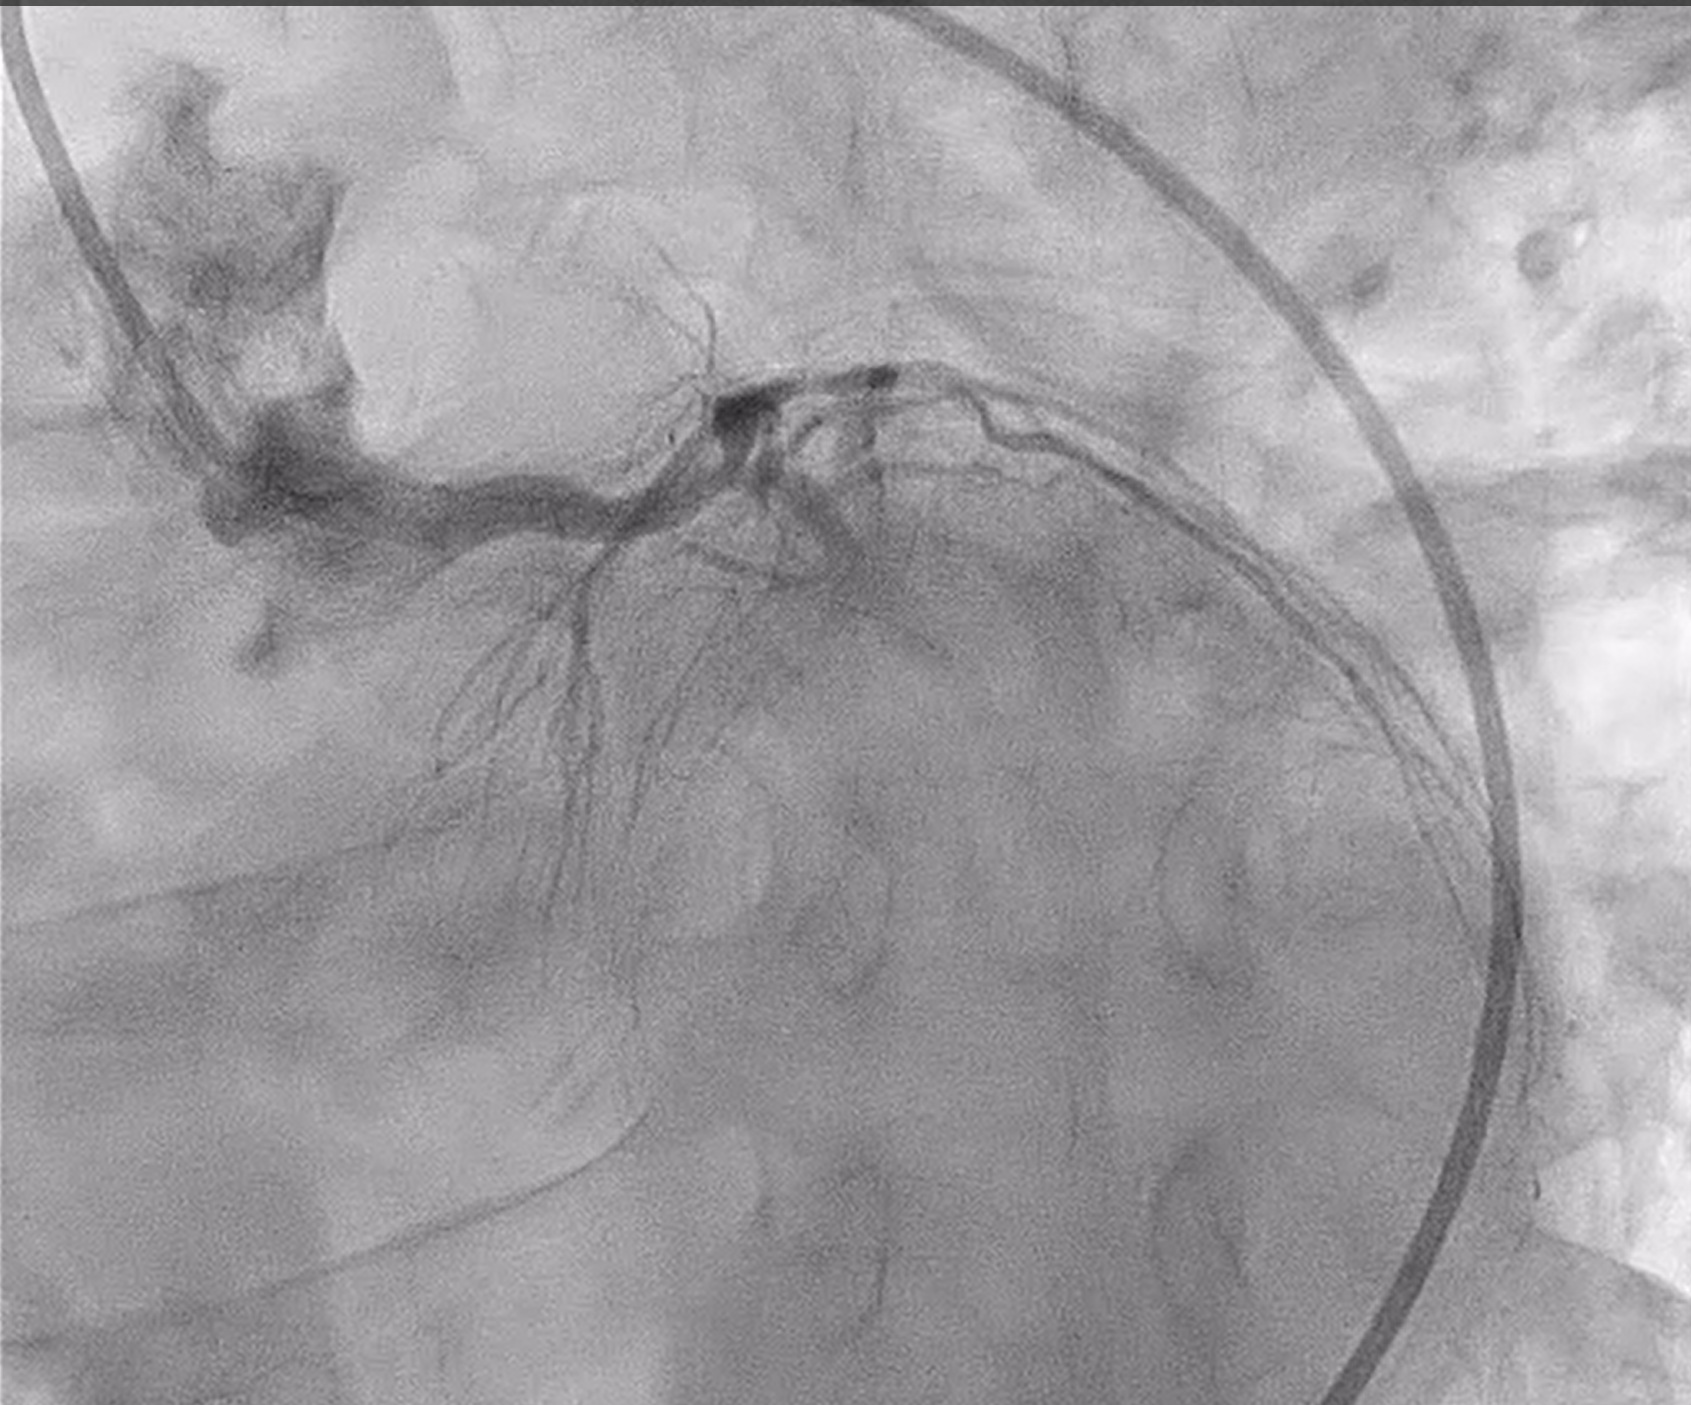

Coronary angiography revealed heavily calcified along LM, proximal to mid LAD, LCx and proximal RCA. 50% stenosis at distal LM bifurcation (Medina 1-1-0). 70% stenosis at proximal LAD and total occlusion at mid LAD. Total occlusion at proximal LCx. No significant stenosis of RCA. There were collateral circulations from septal branch of LAD to distal LAD and from PL to distal LAD and distal LCx.

We performed PCI at CTO LAD and LCx with contralateral injection with antegrade wiring and upfront rotablation at LM, LAD and LCx due to heavily calcified lesion. The 7 Fr EBU 3.5 and 6 Fr JR 4.0 catheter were engaged into LCA and RCA, respectively. We opened the LCx CTO segment using microcatheter with Fielder XT guidewire (GW) then rewire from LCx to distal LAD. The CTO GW was exchange to RotaWire Floppy. Rotablation was done at LM-mid LAD with Burr 1.5 mm and LM-proximal LCx with Burr 1.5 mm. IVUS showed EEL of mid LAD = 2.5 mm, proximal LAD = 4.0 mm, distal LM = 5.5 mm and proximal LCx = 3.5 mm. The lesion of mid LAD was prepared with scoring balloon 2.0/15 mm and LM-proximal LAD with scoring balloon 3.5/15 mm. A 2.5/33 mm stent was deployed from proximal-mid LAD. We decided to stenting the lesion at proximal LCx before stenting the lesion at LM-proximal LAD using provisional one stent and POT-kiss-POT technique. A 3.0/26 mm stent was deployed at proximal LCx. A 3.5/38 mm stent was deployed from distal LM-proximal LAD and 3.5/13 mm stent from ostial LM-distal LM. POT was done with a non-compliance (NC) 5.0/12 mm balloon along LM stent. Kissing balloon inflation with NC 3.0/15 mm balloon at LM-LCx and 3.5/15 mm balloon at LM-LAD then final POT with NC 5.0/12 mm was done. IVUS showed well stent expansion, no malapposition and no stent edge dissection. The patient had no re-admission. Echocardiography after 3 months showed significant improvement of LV function to 56%.